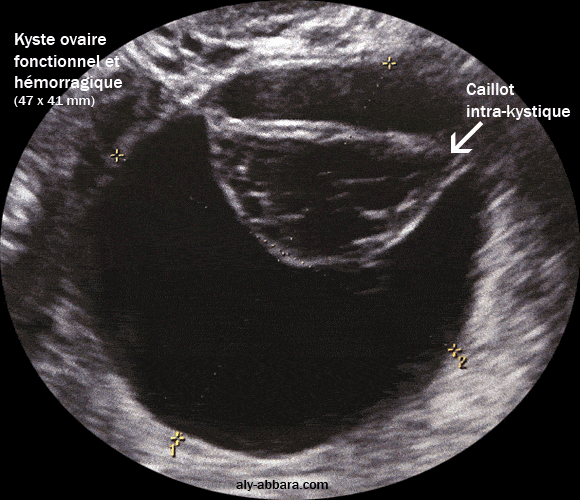

Kyste de l'ovaire droit fonctionnel compliqué d'une hémorragie intrakystique

Il s'agit d'un kyste ovarien droit, uniloculaire, à paroi fine, sans

végétations endophytiques ni exophytiques

; il mesure 47 x 41 mm de diamètre, il disparaît complètement après deux mois d'utilisation d'une

pilule

contraceptive œstroprogestative

à 30 µg d'éthinyl estradiol.